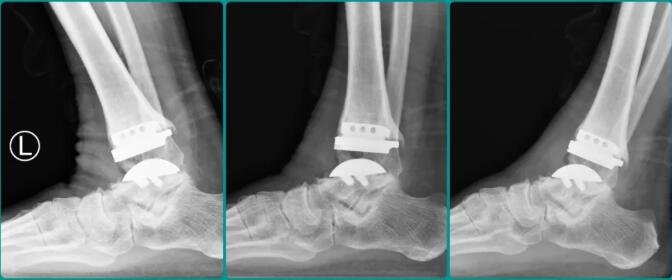

△赵大爷左踝手术前后X光对比。

听说徐州仁慈医院足踝外科有着成熟的人工全踝关节置换技术,赵大爷于2023年初慕名前来。徐州仁慈医院副院长、足踝大科主任石荣剑率领团队认真研判病情后,认为赵大爷具备全踝关节置换的条件。借助3D打印导板等数字化技术辅助,仁慈足踝团队为赵大爷实施了人工全踝关节置换手术。